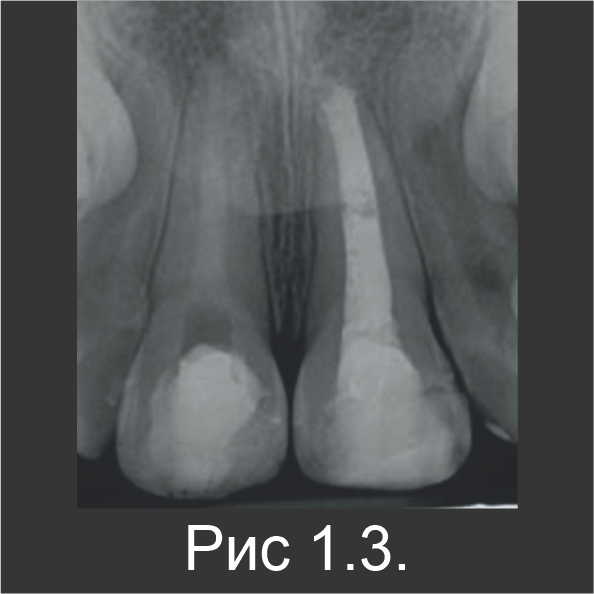

9-летнюю девочку направили для лечения некроза пульпы незрелого зуба 21, который возник в результате травмы, произошедшей несколькими неделями ранее. В область травмирующего воздействия были вовлечены верхние центральные резцы 11 и 21. Когда материала Biodentine™ еще не было, для апексификации в качестве пробки использовали МТА, а поверх нее нанесли гуттаперчу (рис. 1.1). Через три месяца в зубе 11 также обнаружили некроз пульпы. После стандартного промывания канала гипохлоритом натрия без обработки инструментами, зуб 11 запломбировали гидроксидом кальция и оставили на 1 неделю, чтобы затем выполнить лечение с использованием Biodentine™. В течение второго визита эндодонтический канал запломбировали материалом Biodentine™ по всей длине (рис. 1.2).

Сообщений о постоперационной боли не было. По истечении 6-месячного периода наблюдения патологии на рентгенограмме не наблюдались (рис. 1.3). Клинически в зубе 21, который лечили с использованием МТА, определялось небольшое изменение цвета (рис. 1.4). Известно, что MTA может повлечь изменение цвета коронки, а в данном случае – вероятно, из-за остатков МТА в пришеечной зоне. Патологий в апикальной зоне обоих резцов обнаружено не было.